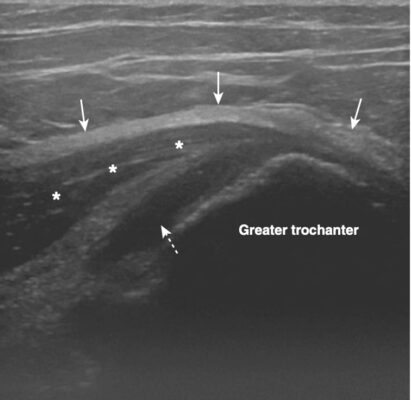

Siêu âm chẩn đoán có giá trị tiên liệu chẩn đoán (PPV) GTPS cao. Các dấu hiệu dương tính bao gồm túi thanh mạc ở mấu chuyển dày và chứa nhiều dịch với bằng chứng của viêm, các dấu hiệu bệnh gân cơ, hoặc rách trong gân cơ mông nhỡ hoặc mông nhỏ..

Hình: Siêu âm mặt phẳng cắt ngang háng ở một bệnh nhân đau mặt ngoài háng. Có dịch nghèo echo trong túi thanh mạc dưới cơ mông nhỡ (mũi tên chấm trắng), nằm giữa cơ và gân mông nhỡ (hoa thị) và diện nhỏ sau ngoài của mấu chuyển lớn. Dải chậu chày ở nông so với cơ mông nhỡ (mũi tên trắng).